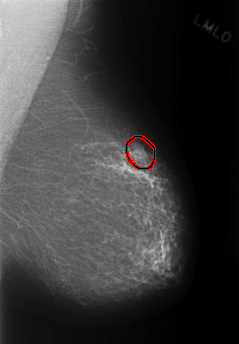

C_0331_1.LEFT_MLO

FILE: C_0331_1.LEFT_MLO.OVERLAY

TOTAL_ABNORMALITIES 1

ABNORMALITY 1

LESION_TYPE MASS SHAPE LOBULATED MARGINS OBSCURED

ASSESSMENT 3

SUBTLETY 5

PATHOLOGY BENIGN

TOTAL_OUTLINES 1

BOUNDARY